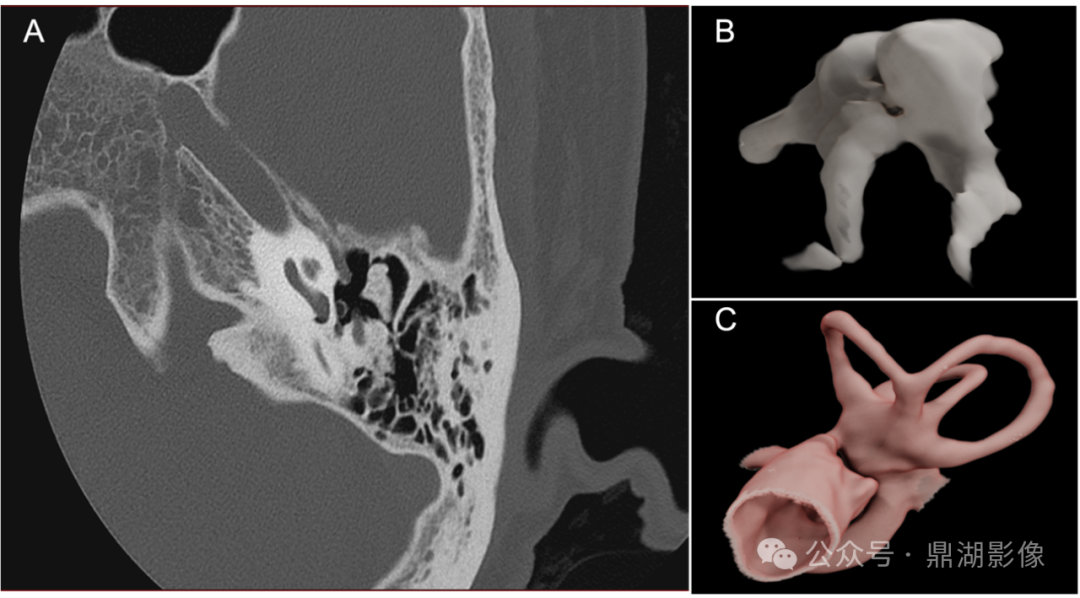

图 内耳高分辨率扫描显示:听小骨(镫骨)结构

NeuViz Epoch Elite通过46.5lp/cm超高空间分辨率可精准评估镫骨形态及毗邻关系,为耳科手术(如镫骨切除术)提供关键解剖信息。

图 内耳超高清扫描及重建精细显示:听小骨、半规管结构